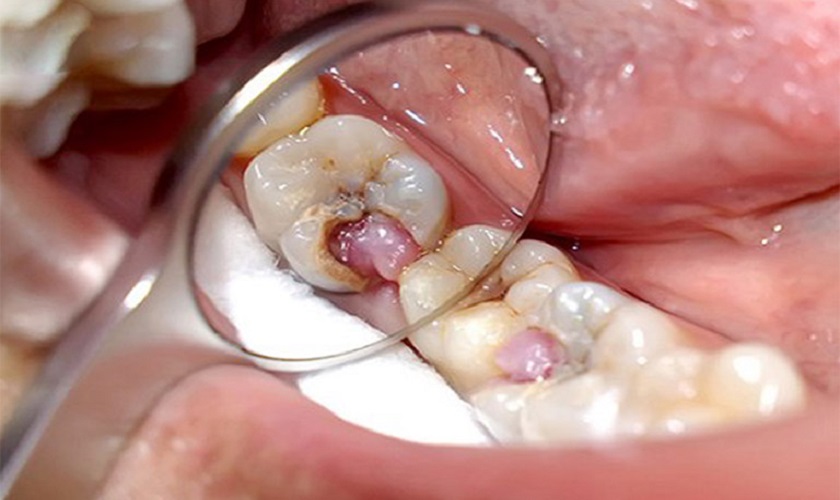

Hiện tượng viêm tủy răng mạn tính

Diệt tủy răng khi bị viêm tủy nếu không tiến hành kịp thời có thể dẫn đến mất răng